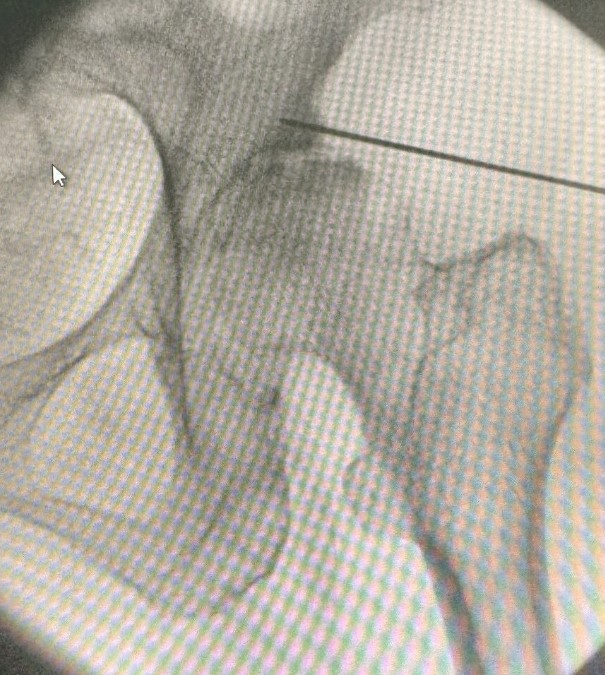

- Σε αρχικά και μέσα στάδια, η νόσος μπορεί να αντιμετωπισθεί με φαρμακοθεραπεία, εγχύσεις κορτιζόνης και υαλουρονικού στην άρθρωση υπό υπερηχογραφική ή ακτινοσκοπική καθοδήγηση και φυσικοθεραπεία.